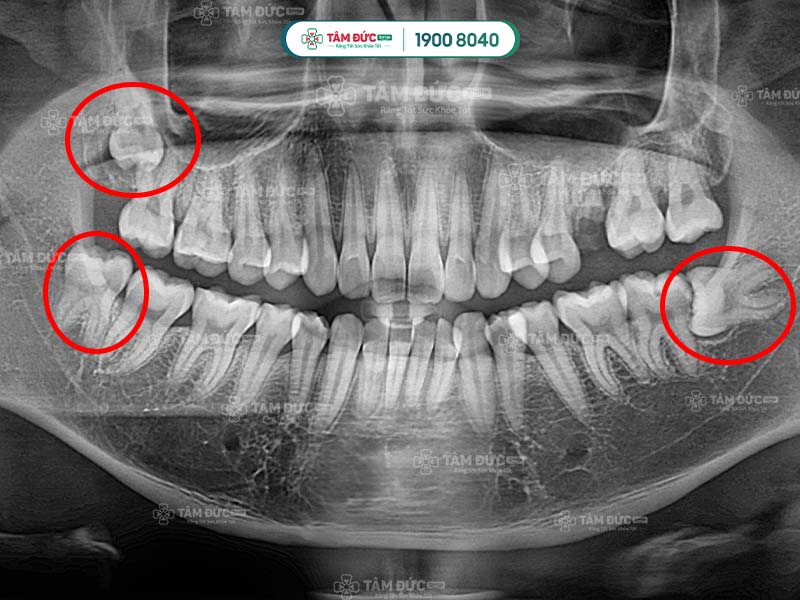

1. Những đặc điểm của răng khôn mọc lệch 45 độ

Dấu hiệu nhận biết Quý khách có răng khôn mọc lệch 45 độ là các cơn đau âm ỉ, kéo dài nhiều ngày. Nguyên nhân là vì khoảng trống trên hàm đã không còn nhiều, vị trí của răng khôn bị ảnh hưởng bởi mô mềm và răng hàm số 7. Điều này đã làm răng mọc nghiêng theo nhiều góc độ so với răng số 7 như 45 độ hay 90 độ.

Răng khôn mọc lệch làm ảnh hưởng răng số 7

Bước 2: Đối với răng khôn mọc lệch, Quý khách cần được chụp X-Quang để xác định hướng mọc, vị trí của chân răng, xương hàm và dây thần kinh.